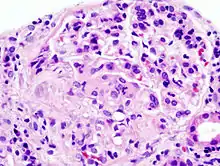

| Histopathological image of crescentic glomerulonephritis in a patient with MPO-ANCA positive rapid progressive glomerulonephritis. Hematoxylin & eosin stain. | |

Rapidly progressive glomerulonephritis (RPGN) is a syndrome of the kidney that is characterized by a rapid loss of kidney function,[4][5] (usually a 50% decline in the glomerular filtration rate (GFR) within 3 months)[5] with glomerular crescent formation seen in at least 50%[5] or 75%[4] of glomeruli seen on kidney biopsies. If left untreated, it rapidly progresses into acute kidney failure[6] and death within months. In 50% of cases, RPGN is associated with an underlying disease such as Goodpasture syndrome, systemic lupus erythematosus or granulomatosis with polyangiitis; the remaining cases are idiopathic. Regardless of the underlying cause, RPGN involves severe injury to the kidneys' glomeruli, with many of the glomeruli containing characteristic glomerular crescents (crescent-shaped scars).[7]

It is thought that antineutrophil cytoplasmic antibodies (ANCA) interact with antigens in the cytoplasm of neutrophils to cause an early degranulation, triggering the release of lytic enzymes at the site of injury[8] and leading to the formation of glomerular crescents that consist primarily of parietal epithelial cells from Bowman's capsule and in some cases podocytes.[9]